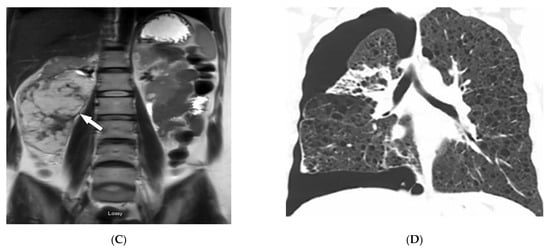

3.12. Peutz–Jeghers Syndrome (PJS)

| Peutz–Jeghers syndrome | Mucocutaneous pigmented macules Hamartomatous polyps | Multiple intraluminal filling defects on barium study |